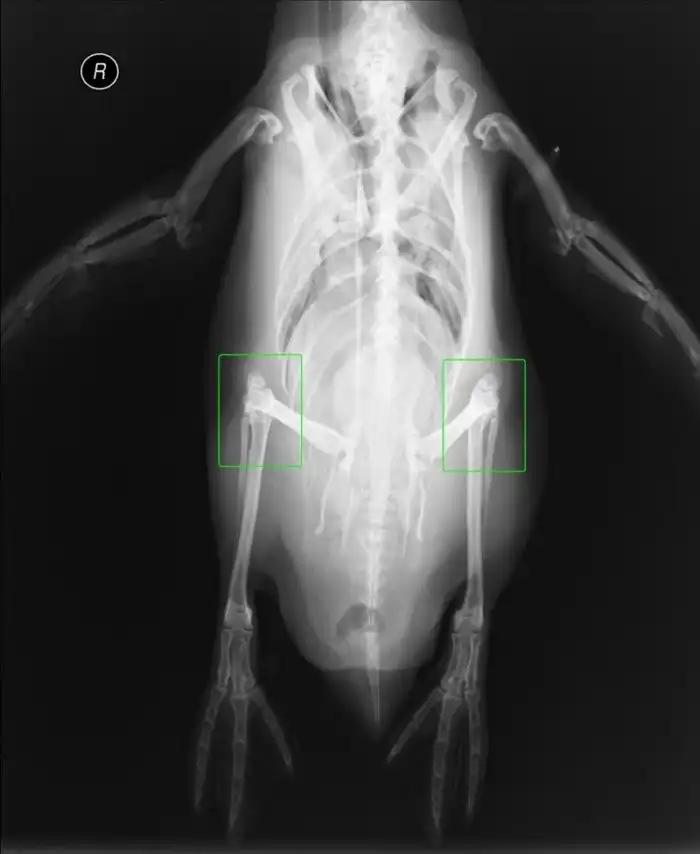

У пингвинов всё-таки есть колени